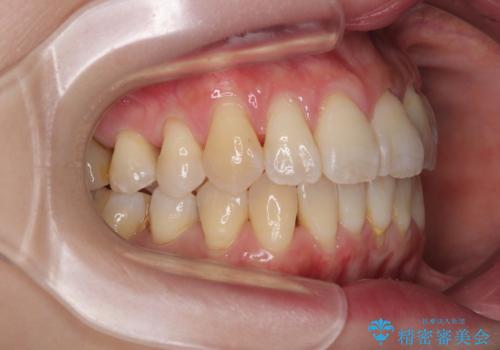

- 上下前歯のデコボコを気にして来院された患者様です。

デコボコは顕著であるものの、口元の突出感は強くないため、非抜歯にて矯正治療を行うこととしました。

元々の叢生と歯肉退縮傾向になる歯肉であったため、ブラックトライアングルが目立つことが想定されました。

治療過程でブラックトライアングル改善のため、IPR(歯と歯の間を削る)を活用しました。